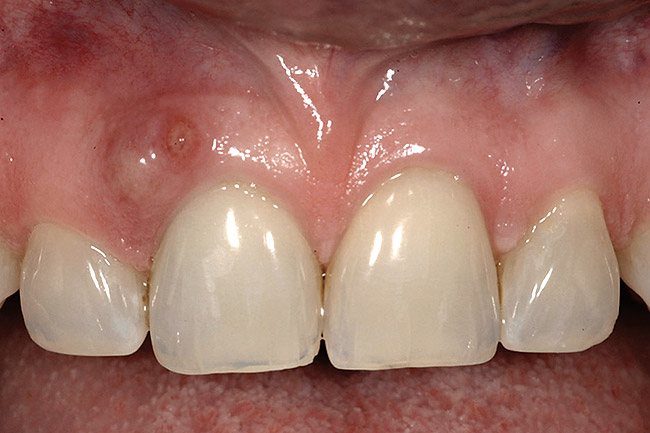

Figure 11  Soft-tissue levels were acceptable at the time of placement of the final restoration.

Figure 11

Figure 12  At 6 months postinsertion, the papilla receded as bone was lost.

Figure 12

Figure 13  Twelve months after placement, soft tissue migrated apically as bone between the implants continued to resorb.

Figure 13